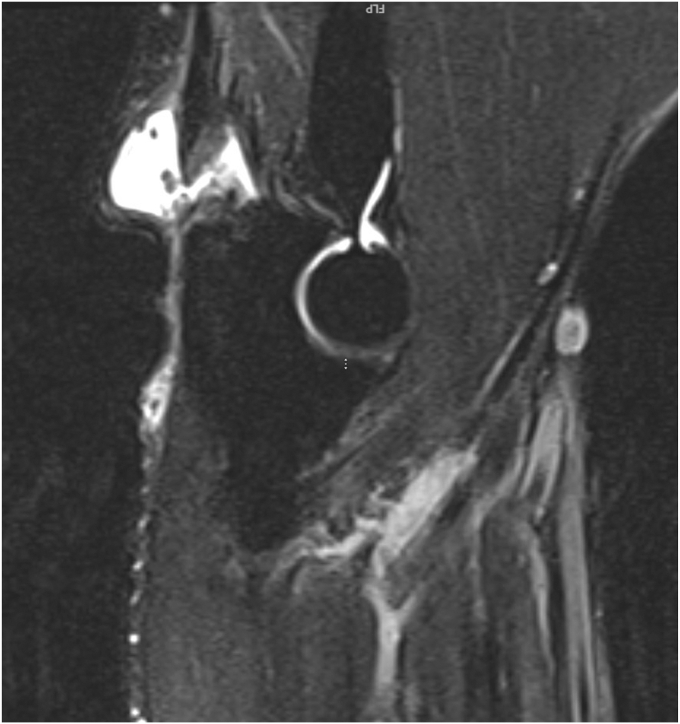

Initial anteroposterior and lateral radiographs of the right elbow demonstrated chronic calcification of the triceps tendon posteriorly (Figs. 1 and 2). A T2-weighted magnetic resonance imaging (MRI) of the right elbow was then performed in order to further evaluate the injury, which was interpreted and reviewed by a fellowship-trained shoulder and elbow orthopedic surgeon. T2-weighted MRI of the right elbow demonstrated a full-thickness tear of the triceps tendon with approximately 5 centimeters of retraction off the distal insertion of the olecranon process with surrounding hyperintense T2 signal (Figure 3, Figure 4, Figure 5). No intra-articular effusion or loose bodies were present, and there was no significant radiocapitellar or ulnohumeral arthrosis. No other abnormalities were noted on the MRI.

Figure 3.

Preoperative magnetic resonance imaging. Sagittal T2-weighted MRI of the right elbow with evidence of full-thickness tear of the triceps tendon with approximately 5 cm of retraction off the distal insertion of the olecranon process and surrounding hyperintense T2 signal.